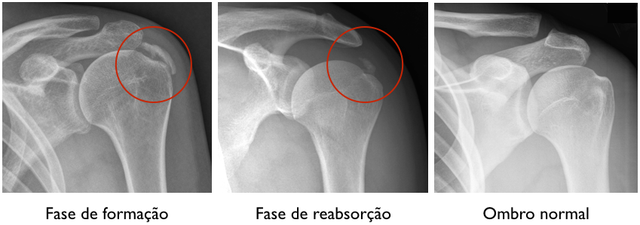

Depois dessa conversa inicial, o próximo passo é o exame físico. O médico vai movimentar seu braço em diferentes posições para ver quais movimentos desencadeiam a dor e onde ela é mais intensa. Ele pode pressionar certas áreas do ombro também. E para ter certeza absoluta, a radiografia (o raio-X) é quase sempre o exame principal. É nessa imagem que as famosas calcificações no tendão aparecem bem visíveis, confirmando o diagnóstico. Às vezes, se houver alguma dúvida, pode ser solicitado um ultrassom, que mostra os tecidos moles com mais detalhes.

A confirmação vem com a imagem certa, mostrando aquelas calcificações que causam a inflamação e a dor no ombro. É importante não se desesperar ao ouvir o diagnóstico. O tratamento para a dor no ombro por tendinite calcária existe e pode trazer muito alívio. Vamos combinar, ninguém merece ficar com dor, né? Buscar ajuda médica logo no início faz toda a diferença.

Falar sobre tendinite calcária no ombro pode parecer assustador, mas entender as fases ajuda muito. Geralmente, começa com uma fase de formação, onde o cálcio começa a aparecer. Depois vem a fase de reabsorção, que é quando o corpo tenta dissolver esse depósito. É nessa fase que a dor costuma apertar mais.

Muita gente me pergunta sobre como lidar com essa dor, especialmente na fase em que o corpo está trabalhando para “limpar” o cálcio. Fica tranquila, porque existem maneiras de aliviar o desconforto enquanto isso acontece. O mais importante é não forçar o movimento que dói, ok?

Depois de um tempo, o corpo consegue reabsorver grande parte do cálcio e a dor vai diminuindo naturalmente. É um processo que varia de pessoa para pessoa, mas a resolução acontece. O segredo é ter paciência e seguir as orientações médicas.

| Fases da Tendinite Calcária: Do Início à Resolução | Geralmente, há uma fase de formação, uma fase de calcificação e uma fase de reabsorção, onde o corpo começa a eliminar o cálcio. A dor é mais comum nas fases de formação e calcificação. | Entender a fase em que você está ajuda a gerenciar as expectativas. Nem sempre a dor intensa significa que o problema é mais grave, às vezes indica que o corpo está agindo. |